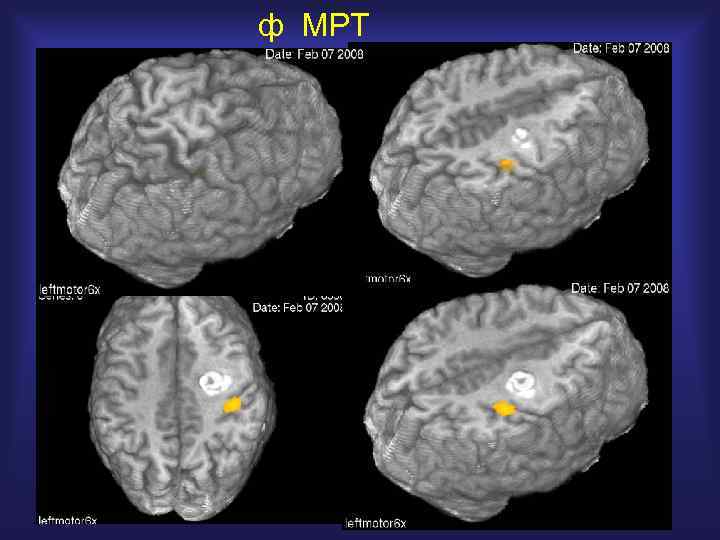

ф МРТ